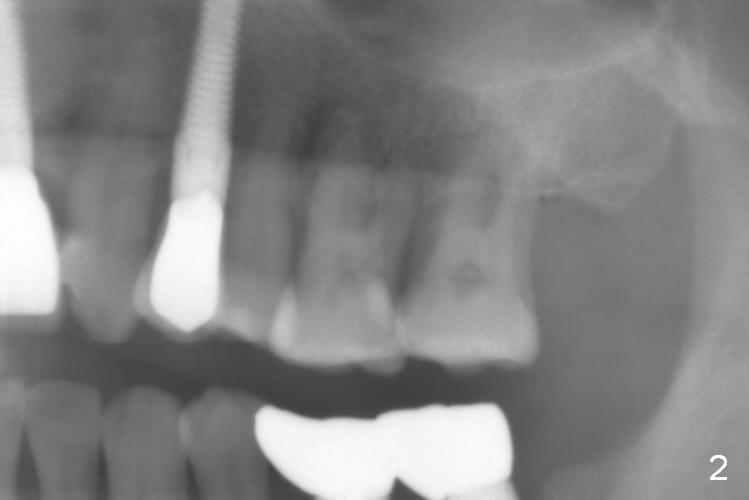

The teeth #14 and 15 of a 42-year-old man are supraerupted when implants are placed at #18 and 19 (Fig.1). Intrusion takes 6 months with 3 mini-implants. Fig.2 is taken 2 years after treatment.